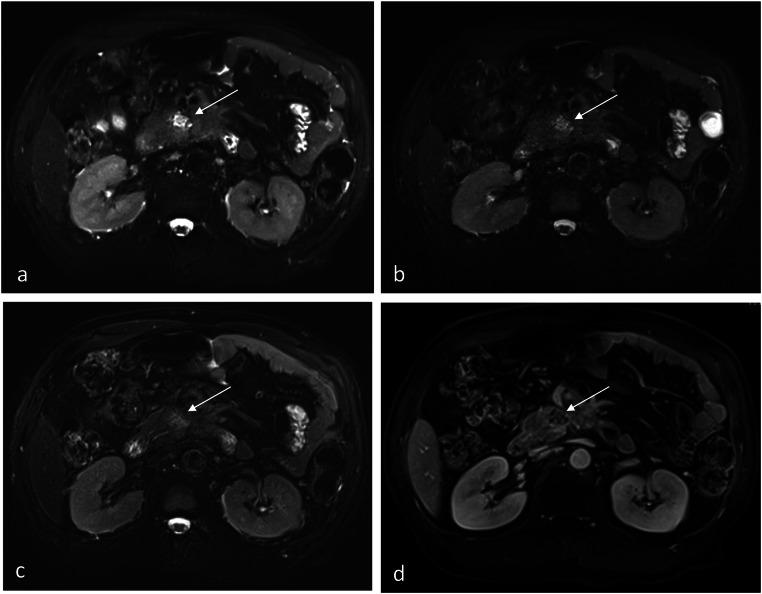

The objective of this study was to evaluate the clinical feasibility of deep learning reconstruction-accelerated thin-slice single-breath-hold half-Fourier single-shot turbo spin echo imaging (HASTE) for detecting pancreatic lesions, in comparison with two conventional T2-weighted imaging sequences: compressed-sensing HASTE (HASTE) and BLADE.

From March 2022 to January 2023, a total of 63 patients with suspected pancreatic-related disease underwent the HASTE, HASTE, and BLADE sequences were enrolled in this retrospectively study. The acquisition time, the pancreatic lesion conspicuity (LC), respiratory motion artifact (RMA), main pancreatic duct conspicuity (MPDC), overall image quality (OIQ), signal-to-noise ratio (SNR), and contrast-noise-ratio (CNR) of the pancreatic lesions were compared among the three sequences by two readers.

The acquisition time of both HASTE and HASTE was 16 s, which was significantly shorter than that of 102 s for BLADE. In terms of qualitative parameters, Reader 1 and Reader 2 assigned significantly higher scores to the LC, RMA, MPDC, and OIQ for HASTE compared to HASTE and BLADE sequences; As for the quantitative parameters, the SNR values of the pancreatic head, body, tail, and lesions, the CNR of the pancreatic lesion measured by the two readers were also significantly higher for HASTE than for HASTE and BLADE sequences.

Compared to conventional T2WI sequences (HASTE and BLADE), deep-learning reconstructed HASTE enables thin slice and single-breath-hold acquisition with clinical acceptable image quality for detection of pancreatic lesions.